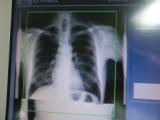

一般撮影ノウハウ

アナログ画像学

CR DR FP CCD Manmmo Graphy